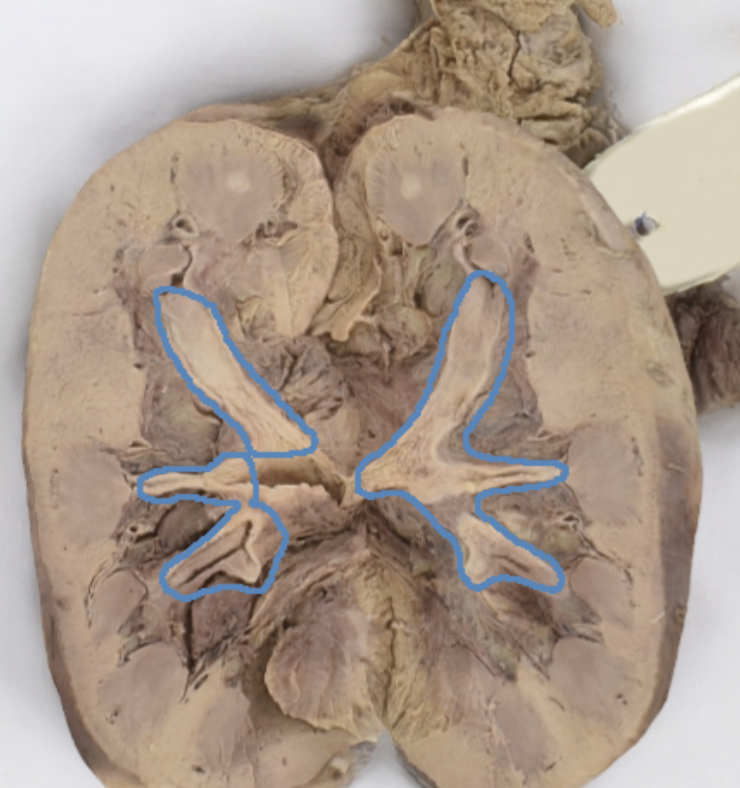

major calyces

blue

renal pelvis

teal

minor and major calyces

renal medulla

renal pyramids

renal lobe

papillary ducts

collecting ducts form [ ], which empty into the minor calyx